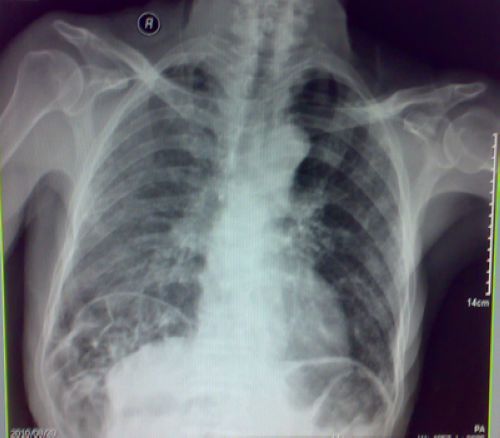

标题: X7847:典型间位结肠(手机照的质量欠佳,见谅) [打印本页]

标题: X7847:典型间位结肠(手机照的质量欠佳,见谅)

肝区间位结肠

右侧间位结肠。

典型,图像欠清,肺内也有问题。

间位结肠 间质性肺炎

肝区间位结肠,肺内也有病变。

间位结肠,图像欠清,肺内也有问题,建议进一步检查。

右侧间位结肠,肺内也有炎症